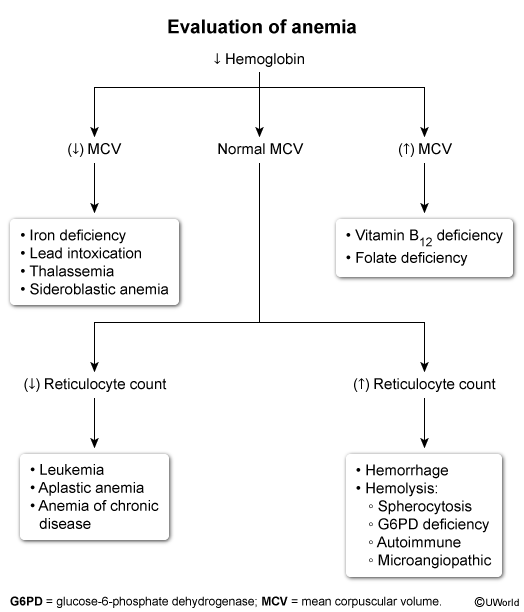

hx of dark urine & anemia, now with hemolytic anemia, jaundince, & splenomegaly and RUQ abdominal pain. does not go to doctor/never been evaluated for this

what’s the chronic condition? what does he have rn and why?

what other treatments should we start?

hereditary spherocytosis d/t deficiency in tbc scaffolding proteins (spectrin, ankyrin)

↑ mean corpuscular hemoglobin concentration due to membrane loss & rbc dehydration

RUQ pain due to pigment gallstones → cholecystitis

ggive folate (chronic hemolysis consumes it) & may require splenectomy